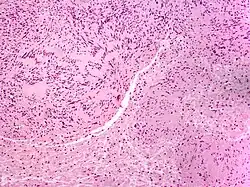

Micrograph of a palisaded encapsulated neuroma | |